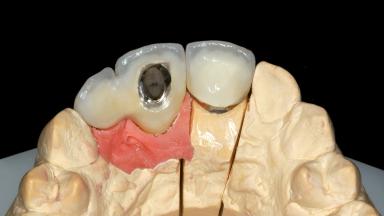

| Abutment Type | Customized |

| Prosthesis Type | FDP |